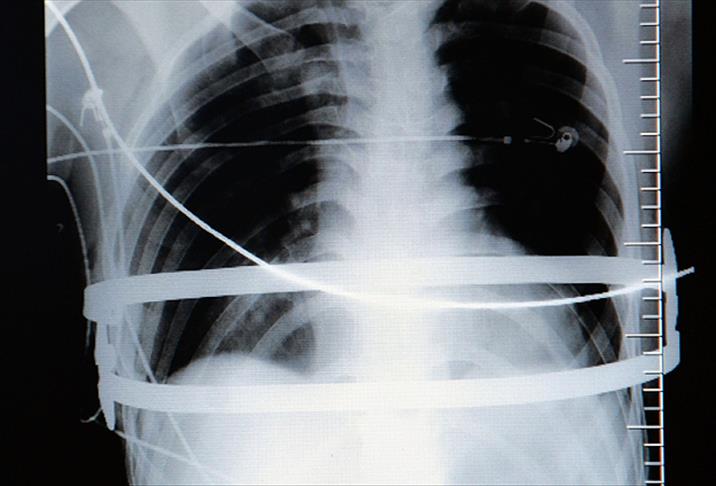

Gerekli malzeme temini ve hazırlıklar yapıldıktan sonra hasta ameliyata alındı. Hastanın iki tarafından 3 santimetrelik kesiler açılarak 100'er gramlık 2 çelik bar, kalp ve iman tahtası arasından geçirilerek vücuda yerleştirildi ve çöküklük ortadan kaldırıldı. "Çelik barlar iki yıl sonra çıkartılacak"

Ameliyatı gerçekleştiren göğüs cerrahisi uzmanı Opr. Dr. Oktay Aslaner, gazetecilere yaptığı açıklamada, göğüs bölümünde çöküklüğün fazla olması nedeniyle 2 çelik bar kullanmak zorunda kaldıklarını söyledi.

"Hastamızı en son yöntemle kapalı şekilde ameliyat ettik. Kalple iman tahtasının arasından bar geçirip daha sonra ters çevirerek öndeki kemiği yukarıya kaldırmış olduk. Hastayı ameliyattan bir gün sonra servise aldık. Şimdi taburcu olabilecek seviyede. Göğsündeki metaller 2 yıl kadar kalacak. Normalde bu hastaları biraz daha erken yaşlarda ameliyat etmek gerekiyor. Şimdi hem estetik olarak düzeldi, hem de bizim açımızdan önemli olan, kalbe ve akciğerlere yapılan bası ortadan kalkmış oldu."

Yaklaşık 1,5 saat süren ameliyatın başarılı geçtiğini ifade eden Sağlam, "Barların çeşitli boyutları vardı. Önce hastanın göğsüne koyacağımız barların ölçüsünü aldık. Ameliyata başlamadan bu ölçüye göre barlara şekil verdik. Daha sonra operasyonu gerçekleştirdik" dedi.